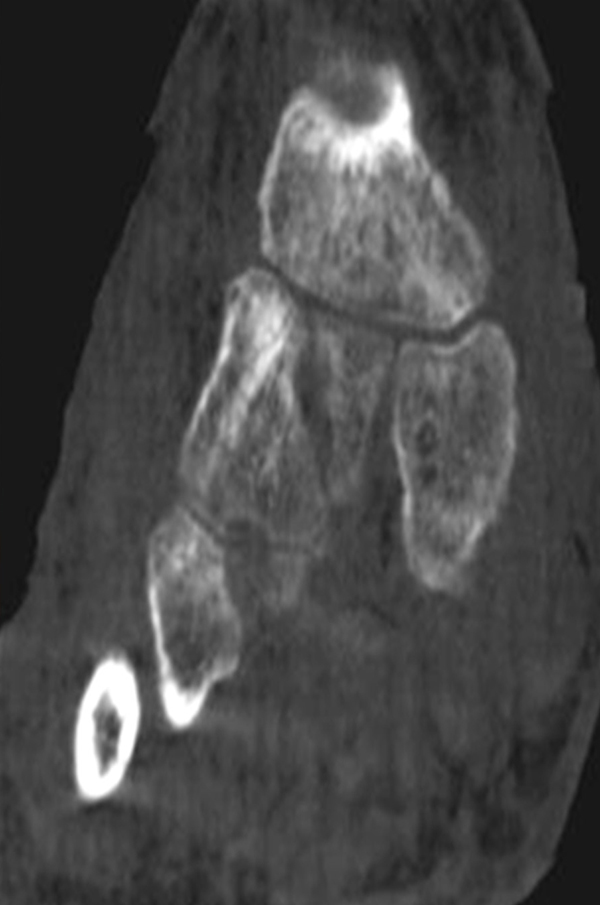

SPECT/CT bei Coalitionen

Coalitionen sind nicht-gelenkige Verbindungen zwischen Fußwurzelknochen. Es gibt drei verschiedene Typen: fibröse Coalitio (= Syndesmose), knorpelige Coalitio (= Synchondrose) und knöcherne Coalitio (= Synostose), wobei die Inzidenz von tarsalen Coalitionen bei ca. 1 % liegt und in der Hälfte der Fälle bilateral auftritt (Freyschmidt, 2001) 6. Am häufigsten (90 %) sind die calcaneonaviculare und die talocalcaneare Coalitio. Talonaviculare und calcaneocubidale Coaltionen sind sehr selten. Extrem selten ist eine Verbindung zwischen Os naviculare und Os cuboideum 414243 (Freyschmidt, 2002).

Coalitionen können auf Röntgenbildern wegen überlappender Strukturen häufig nicht sicher diagnostiziert werden, so dass MRT und/oder CT erforderlich sind, um eine Coalitio eindeutig nachzuweisen. Der Vorteil der SPECT/CT liegt darin, dass neben der submilimeter-genauen Darstellung der Anatomie, womit die charakterischten Röntgenzeichen einer Coalitio erkannt werden, auch die Stressreaktion bzw. die Scherkräfte, die auf die Syndesmose oder Synchondrose wirken, sichtbar gemacht werden können. Dabei hat die SPECT/CT eine deutlich höhere Treffsicherheit als die MRT zur exakten Lokalisation der Stressreaktion 44.

Abbildung 4.1.zeigt das Beispiel einer Patientin mit einer Stressreaktion zwischen Processus anterior calcanei und Os naviculare, welche einer fibrösen symptomatischen Coalitio entspricht, die primär in der Bildgebung (Röntgen, MRT) nicht erkannt wurde. Bei Knick-Senk-Fuß erfolgte zunächst eine Talo-Naviculare Arthrodese. Postoperativ nahmen die Schmerzen zu. Anstelle eines SPECT/CT erhielt die Patientin zwei Serien einer Röntgen-Reiz-Bestrahlung. Die Patientin stellte sich in einer auf Fußerkrankungen spezialisierten Klinik vor, die die Patientin zur weiteren Abklärung zu uns überwies. Erst die Abklärung mittels SPECT/CT zeigte die eine fibröse Coalitio zwischen Processus anterior calcanei und Os naviculare bei vollständig reizlos durchbauter Talo-Navicularer Arthodese. Es wurde daraufhin eine erfolgreiche konservative Therapie u. a. mittels gezielten Injektionen und Stosswellen eingeleitet.

Die Abbildungen 4.2.a bis d zeigen den typischen Aspekt einer talacalcanearen Coalitio. Es besteht nur eine linksseitige, symptomatische Coalitio talocalcaneare (4.2.a und c); das 35 Tage zuvor angefertigte MRT zeigt keine auffälligen Signalveränderungen (4.2.b und d).

Abbildung 4.3. zeigt die Ursache für rechtsseitige Sprunggelenksbeschwerden bei einem Patienten mit talocalcanearen Coalitionen: nur die osteochondrale Läsion an der distalen rechten Tibia ist die Ursache des Schmerzes. Die bilateralen talocalcanearen Coalitionen sind asymptomatisch.